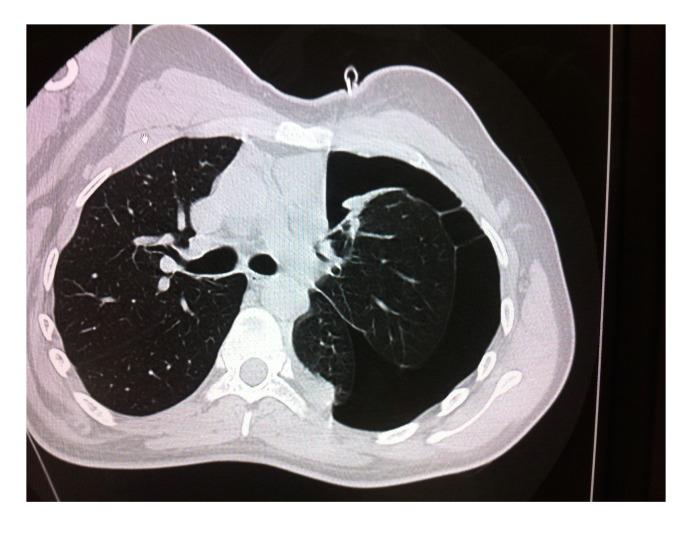

We included in this case report a 25-year-old male who suddenly crossed a road while playing Pokémon Go and was hit by a van, reporting several injuries and being assisted by the Emergency Medical Service of our hospital (Padova, Italy). The patient's history, the circumstances in which the collision happened, imaging data, and clinical course information were recorded per our hospital's privacy policy.

本病例报告纳入一名25岁男性,他在玩《精灵宝可梦Go》时突然横穿马路,被一辆货车撞到,多处受伤,由我院(意大利帕多瓦)的紧急医疗服务部门救治。根据我院隐私政策记录了患者病史、碰撞发生时的情况、影像数据及临床病程信息。